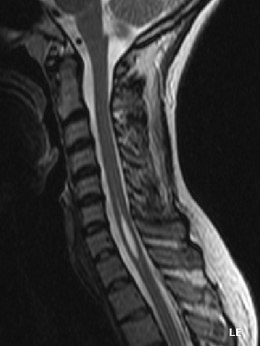

La syringomyélie se caractérise par la formation d’une ou de plusieurs cavités à l’intérieur de la moelle épinière, pouvant causer des douleurs chroniques sévères, des troubles neurologiques et un handicap moteur allant jusqu’à la perte d’autonomie. Ces cavités appelées « syrinx » endommagent les fonctions neurologiques de la moelle épinière. Elle résulte souvent d’une malformation de Chiari et sa prévalence est d’environ 8 personnes sur 100 000. (1)

Dans la moitié des cas environ, la syringomyélie trouve son origine dans une malformation congénitale connue comme la malformation de Chiari. C’est une malformation d’une partie du système nerveux au niveau du cervelet qui, placé anormalement bas, perturbe l’écoulement du liquide céphalo-rachidien autour de la moelle épinière. Le liquide se fraie alors un chemin à l’intérieur de la moelle épinière et forme des cavités. Le liquide céphalo-rachidien (aussi appelé liquide cérébro-spinal) protège le système nerveux central contre les chocs et irrigue les cellules du cerveau en éléments essentiels.